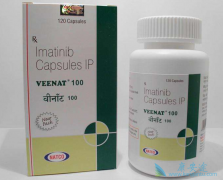

格列卫是因电影《我不是药神》而引起的,格列卫是治疗白血病因此产生活跃的药物,然而 慢粒性细胞白血病 毒格列卫很熟悉吧。格列卫有两个版本,一种是印度版格列卫,另一种是瑞士诺华制药的原版格列卫。今天主要来了解下印度版格列卫对于白血病患者的疗效及 ...